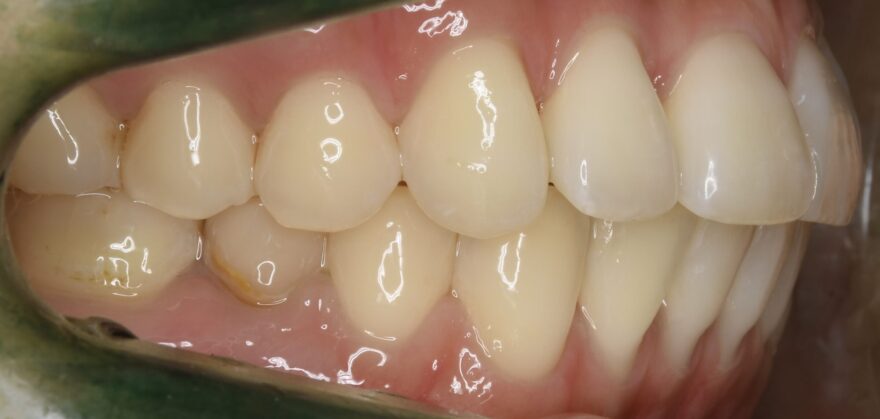

治療後の口腔内写真

約2年半の動的期間(歯を動かす時期)で、ここまで美しい歯並びになりました。

歯科矯正用アンカースクリュー無しだと、治療期間は更に1年長くなってしまったと思います。

前歯の捩れも無くなりました。